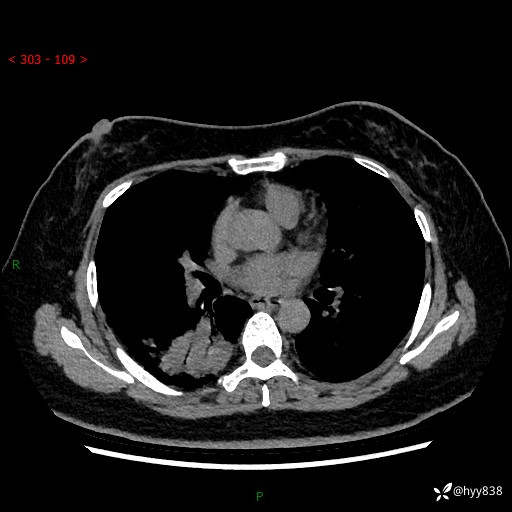

增强动脉期+静脉期